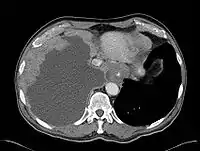

Mesothelioma Overview

- Malignant Mesothelioma